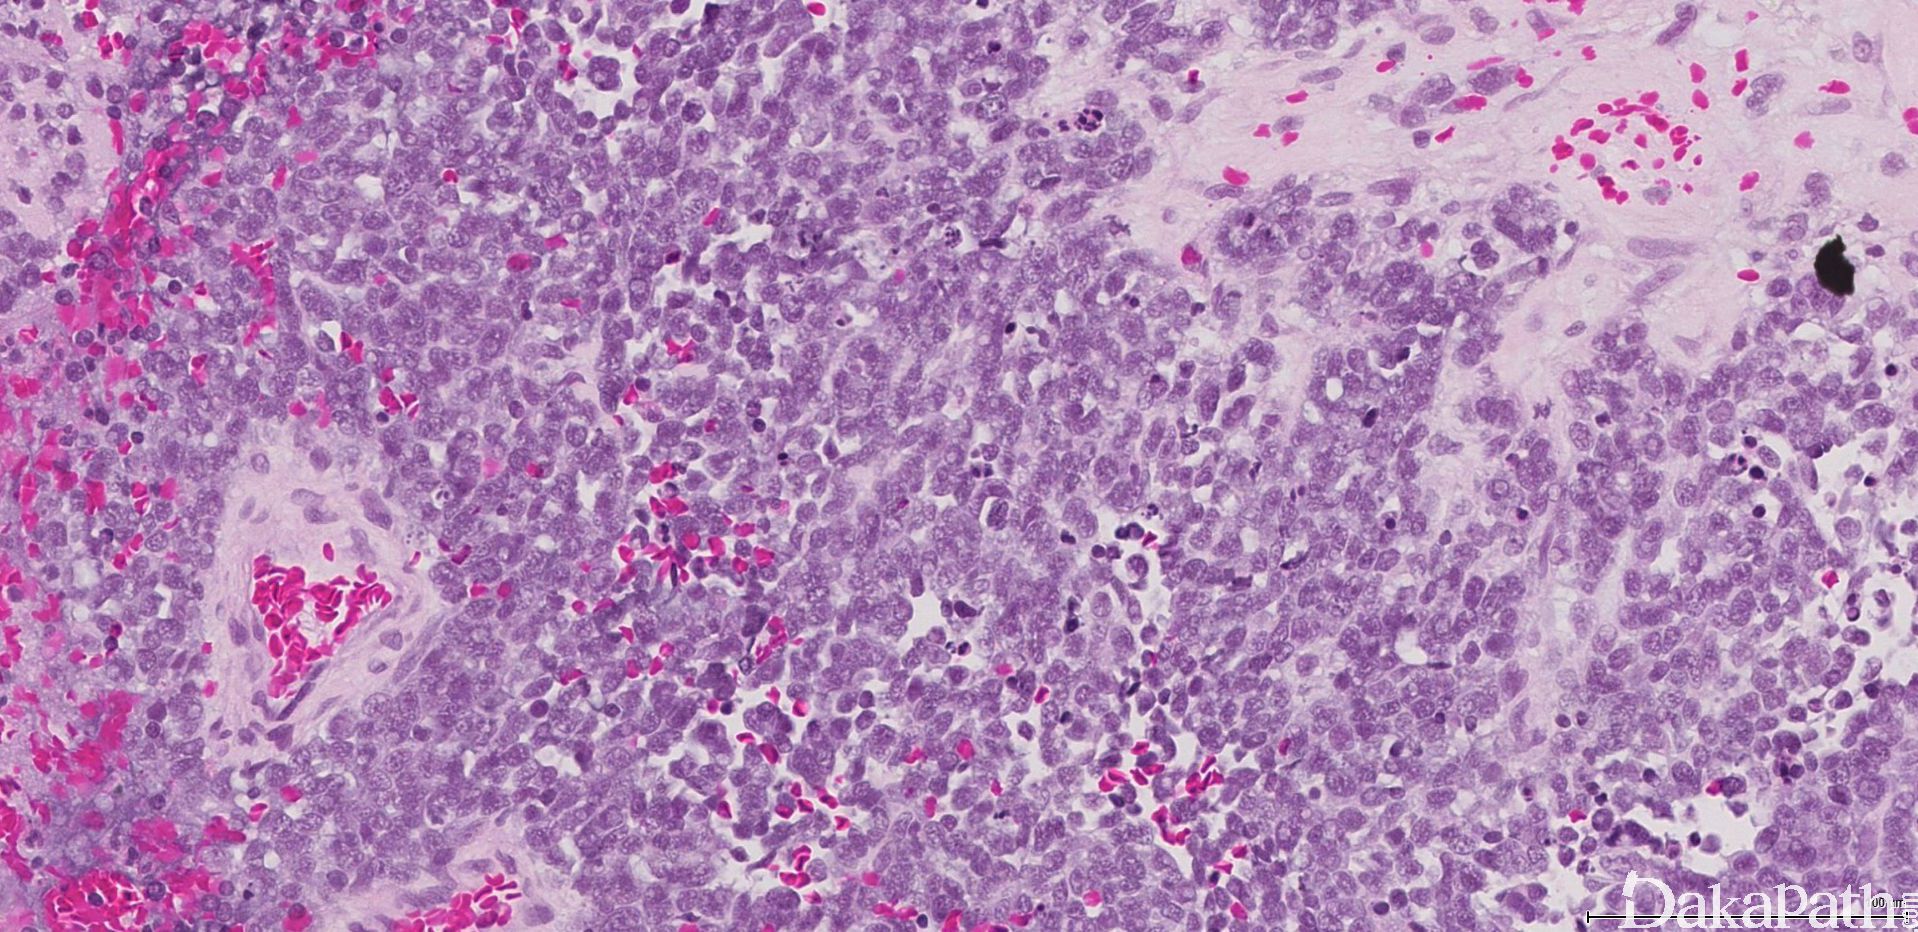

肿瘤细胞呈经典小圆蓝细胞,比成熟淋巴细胞稍微大一些,核浆比高,小而一致的胞核伴细致、椒盐样染色质分布,胞核比较小或缺席。细胞呈合胞体样。可见中央为神经丝状物构成的菊形团(Homer Wright)。

根据分化的程度、神经间质的多少、核分裂像及坏死将肿瘤分成 4 级(Hyams Grading)。1 级:叶状分布,细胞合胞体样,可见神经丝样基质,染色质空泡状,无核分裂及核仁。2 级:神经丝基质变少,核分裂散在。3 级:细胞多形性,真菊形团可见,出现坏死。4 级:显著异型性、核分裂像及坏死。

根据核多形性、核分裂及坏死的有无将肿瘤分为低级别病变(1 级或 2 级)及高级别病变(3 级或 4 级)。核多形性、核分裂及坏死在低级别一般缺如,而在高级别中出现。

可见两种菊形团形式:假菊形团 (Homer Wright)及真菊形团(Flexner-Wintersteiner)。假菊形团见于 30%的病例,肿瘤细胞栅栏状、套样围绕在神经丝样、水肿样神经基质的周围,可见于 1 级或 2 级。真菊形团见于 5%的病例,中空导管样伴非纤毛样柱状细胞,可见与 3 级或 4 级。围血管性菊形团没有诊断价值。